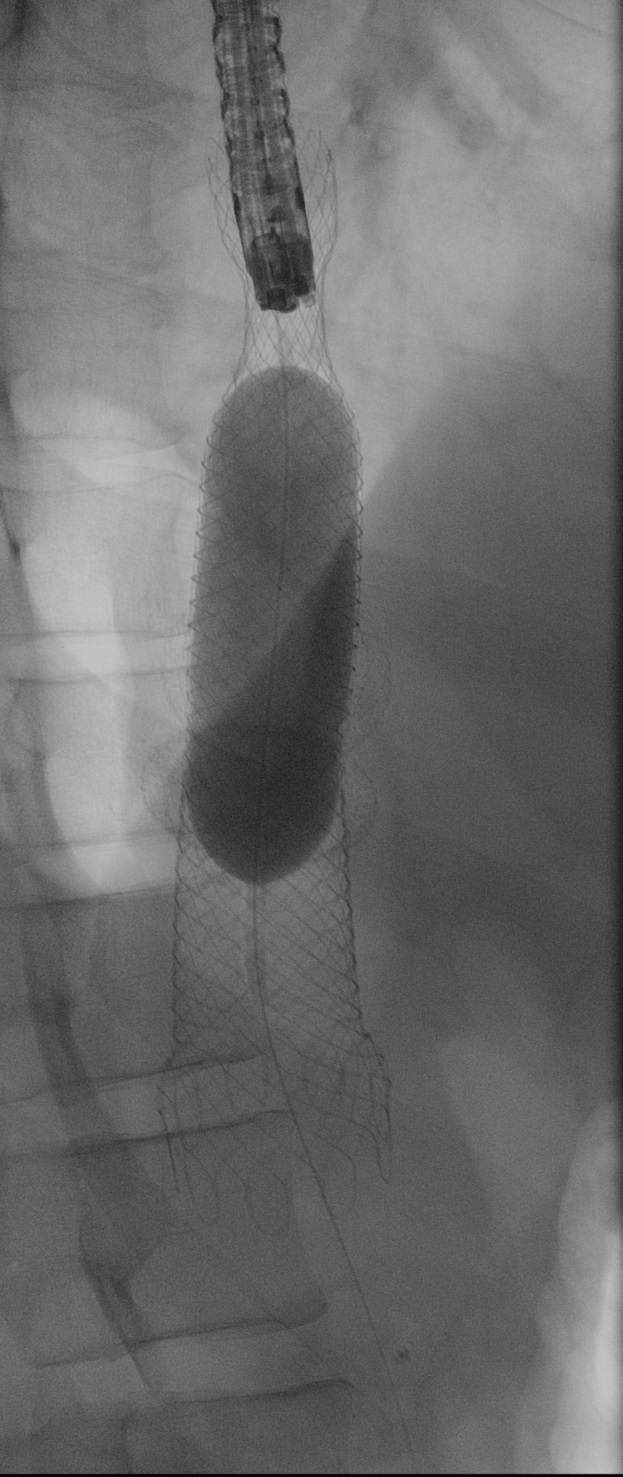

EDGE procedure: esophageal stent to the rescue (2.º Classificado - Vídeo)

Joel Ferreira-Silva, Filipe Vilas-Boas, Eduardo Rodrigues-Pinto, Pedro Pereira, Guilherme Macedo

Centro Hospitalar Universitário de São João

A 39-years-old woman with history of Roux-en-Y gastric bypass was referred to us due to new onset jaundice caused by a pancreatic head adenocarcinoma. Endoscopic ultrasound directed transGastric ERCP (EDGE) was pursued. A 20mm lumen-apposing metal stent (LAMS) was placed between gastric pouch and gastric remnant. Endoscopic retrograde cholangiopancreatography was performed 1 week later. However, LAMS position did not allow duodenoscope passage. A 23x125mm fully-covered metal stent was deployed in a trans-LAMS position, modifying LAMS positioning and allowing passage into gastric remnant. Subsequent biliary cannulation allowed biliary metal stent deployment. Esophageal stent was then removed and LAMS remained in situ.